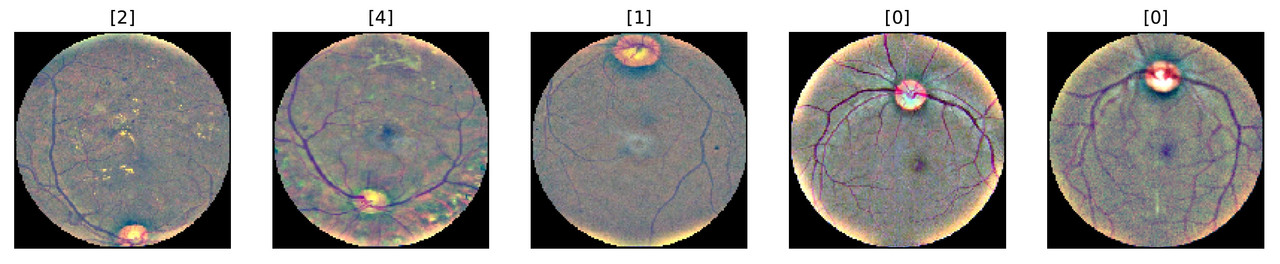

The illustration further emphasizes differences in the aspect ratio and lighting conditions.

The severity of DR is diagnosed by the presence of visual cues such as abnormal blood vessels, hard exudates and so-called cotton wool spots. You can read more about the diagnosing process here. Comparing the sample images, we can see the presence of exudates and cotton wool spots on some of the retina images of sick patients.

This looks much better! Comparing the retina images to the ones before the preprocessing, we can see that the apparent discrepancies between the photos are now fixed. The eyes now have a similar circular shape, and the color scheme is more consistent. This should help the model to detect the signs of the DR.